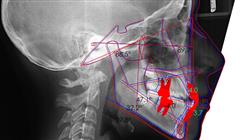

Faça o diagnóstico, descreva, classifique e planeje o tratamento de maloclusões, distinguindo entre problemas esqueléticos e dentários”

A ortodontia tornou-se um ramo da Odontologia que estuda, previne e corrige alterações no desenvolvimento, na posição dos maxilares e no formato das arcadas dentarias,arcadas dentárias, a fim de criar um equilíbrio morfológico e funcional na boca e no rosto. Para isso, possui diferentes tratamentos nos quais busca a normalização oclusal ou o deslocamento de todo o conjunto de dentes.

Todos os itens acima estabelecem a base para o desenvolvimento deste programa, pois a demanda atual está aumentando a cada ano. Dessa forma, e a partir de uma perspectiva teórica e prática, o aluno será capaz de identificar os distúrbios que requerem tratamento, bem como a idade ideal para lidar com cada tipo de distúrbio, identificando os objetivos terapêuticos específicos de cada tratamento.

Na primeira parte deste Mestrado Semipresencial, serão abordados os conceitos teóricos que ajudarão os alunos a entender os protocolos de atendimento das diferentes deformidades e os princípios envolvidos na recuperação fisiológica na recorrência de maloclusões. Depois, na modalidade prática, o aluno irá a um centro especializado para trabalhar em um ambiente real com pacientes que precisam de tratamento ortodôntico. Para isso, ele começará realizando uma série de atividades que envolvem o registro de dados para o prontuário médico e o desenvolvimento de um plano de tratamento adaptado às necessidades da pessoa.

Nesta proposta de Mestrado Próprio, de natureza profissionalizante e modalidade de aprendizagem semipresencial, o programa tem como objetivo atualizar os profissionais de odontologia que desejam desenvolver suas habilidades em Ortodontia e Ortopedia Facial. Os conteúdos são baseados nas mais recentes evidências científicas e são orientados de forma didática para integrar o conhecimento teórico à prática odontológica, e os elementos teórico-práticos facilitarão a atualização do conhecimento e permitirão a tomada de decisões no manejo do paciente.